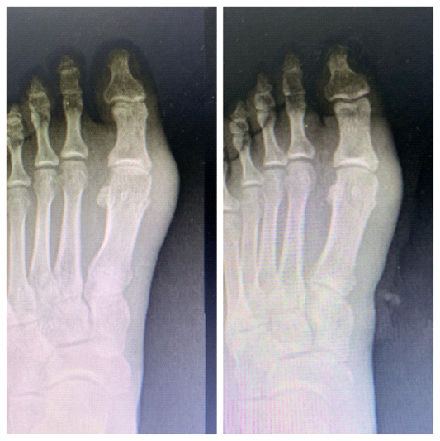

术前X片与术后X片比较